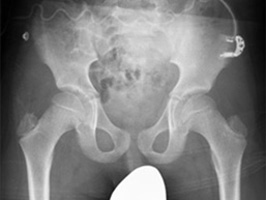

A grid-less workflow with SkyFlow Plus.